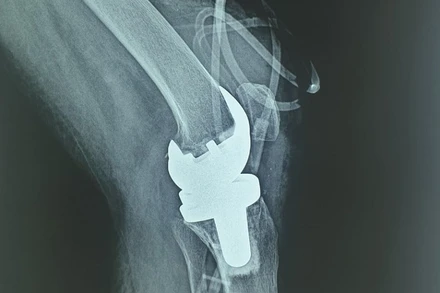

Mảnh ghép titanium in 3D thay thế xương chày cho bệnh nhân. (Ảnh: BVCC)

Y tế

Lần đầu tiên sử dụng mảnh ghép 3D hợp kim titanium dạng tổ ong thay thế xương chày

Ngày 5-1, Khoa Chấn thương chỉnh hình, Bệnh viện Chợ Rẫy cho biết đã phẫu thuật thành công cho một trường hợp bệnh nhân bị mất một đoạn xương chày (do ung thư xương) bằng kỹ thuật "sử dụng mảnh ghép in 3D hợp kim titaninum dạng tổ ong để thay thế xương chày mất đoạn". Đây là trường hợp đầu tiên sử dụng kỹ thuật này tại Việt Nam.